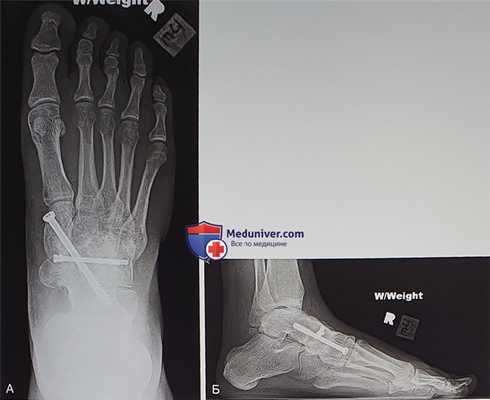

Рисунок 10

5 этап:

- Существует несколько вариантов фиксации трансплантата. Несколько 4,0 мм винтов, проведенных в поперечном направлении, позволят сжать трансплантат между медиальной и латеральной порциями ладьевидной кости и послужат профилактикой продольного расщепления трансплантата. Если ладьевидная кость уже расколота, винты обеспечат ригидную фиксацию ее латеральной и медиальной порций

- Со стороны медиальной клиновидной кости в таранную кость вводится длинный канюлированный винт, обеспечивающий значительную стабильность и компрессию (рис. 10)

- Еще одним вариантом фиксации является использование нескольких небольших винтов и/или пластин. Тыльные пластинки, однако, будут ощущаться под кожей и после формирования костного блока нуждаются в удалении